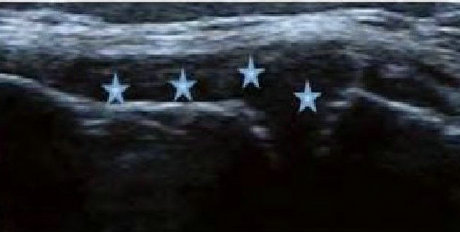

2、清晰显示滑膜异常形态,定量评估RA炎性

类风湿性关节炎以滑膜炎为基本病理改变,超声可观测到关节暗区的范围及厚度,判断有无滑膜增厚、显示不同程度的滑膜均匀或不均匀增厚,分辨滑膜呈绒毛状、团状或结节状结构向关节腔突起的形态。通过对滑膜厚度、水肿、炎性细胞浸润状况的分级、定量评估RA关节内滑膜的炎性程度。

Ⅰ级滑膜增生

轻度滑膜增生,不超过骨面点连线

Ⅱ级滑膜增生

滑膜增生超过骨面点连线,呈绒毛状,但不越过骨干

Ⅲ级滑膜增生

滑膜增生超过骨面点连线,呈团块状延伸超过一侧骨干